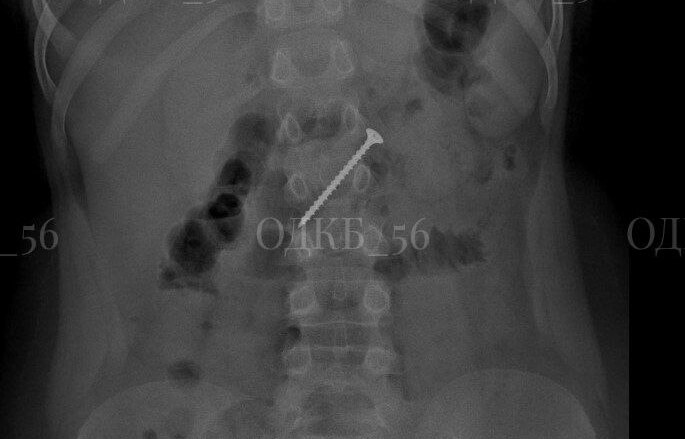

ок проглотил кольцо

Ребенок проглотил кольцо 116 фото